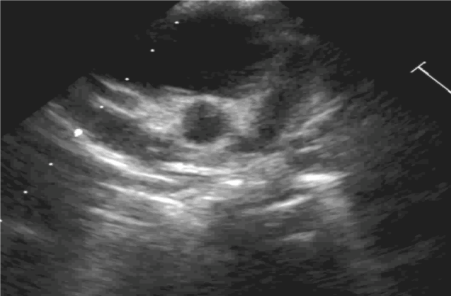

His echocardiogram 2 days later showed diffuse dilation of both coronary arteries, with pericardial effusion. His remittent fever with continued inflammatory activity warranted a second dose of IVIG followed by pulse methyl prednisolone and infliximab (a monoclonal antibody against tumor necrosis alpha) infusion. The boy experienced a recurrence of fever with leukocytosis, thrombocytosis, and elevation of inflammatory markers. An electrocardiogram showed diffuse ST elevation, suggesting pericarditis. A repeat echocardiogram showed persistent diffuse dilation of the entire right coronary artery measuring 11 mm from origin to crux and also extending into the posterior descending coronary branch. The proximal and mid left anterior descending coronary artery (LAD) measured 9 mm, together with ectasia of the left main coronary artery as well as the proximal and mid left circumflex artery (Figures 1&2).

Figure 1. Parasternal short-axis view of the dilated left coronary artery. The proximal left anterior descending coronary artery (LAD) is aneurysmally dilated, and the left circumflex artery (Cx) also is diffusely dilated

Figure 2. Parasternal short-axis view at the level of the aortic root demonstrating a proximal right coronary artery (RCA) aneurysmally dilated